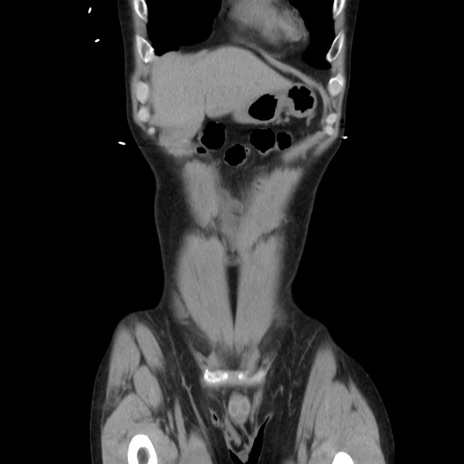

症例37(冠状断像)

横断像